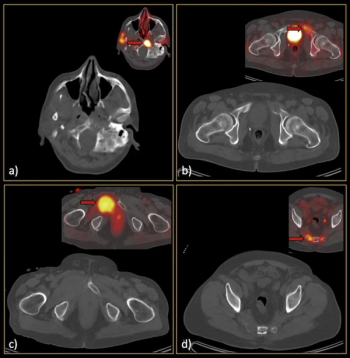

For patients initially diagnosed with non-metastatic, castration-resistant prostate cancer, pelvic lymph node involvement and five or more polymetastases detected with prostate-specific membrane antigen (PSMA)/ positron emission tomography (PET) are significantly associated with lower overall survival rates, according to recently presented research at the American Society of Clinical Oncology (ASCO) conference.

Reportedly the first FDA-approved PSMA PET agent with proprietary radiohybrid technology, POSLUMA can be utilized for positron emission tomography (PET) scans of prostate-specific membrane antigen (PSMA) positive lesions in men with prostate cancer and suspected metastasis, and those with suspected prostate cancer recurrence based on an elevated serum prostate-specific antigen (PSA) level.